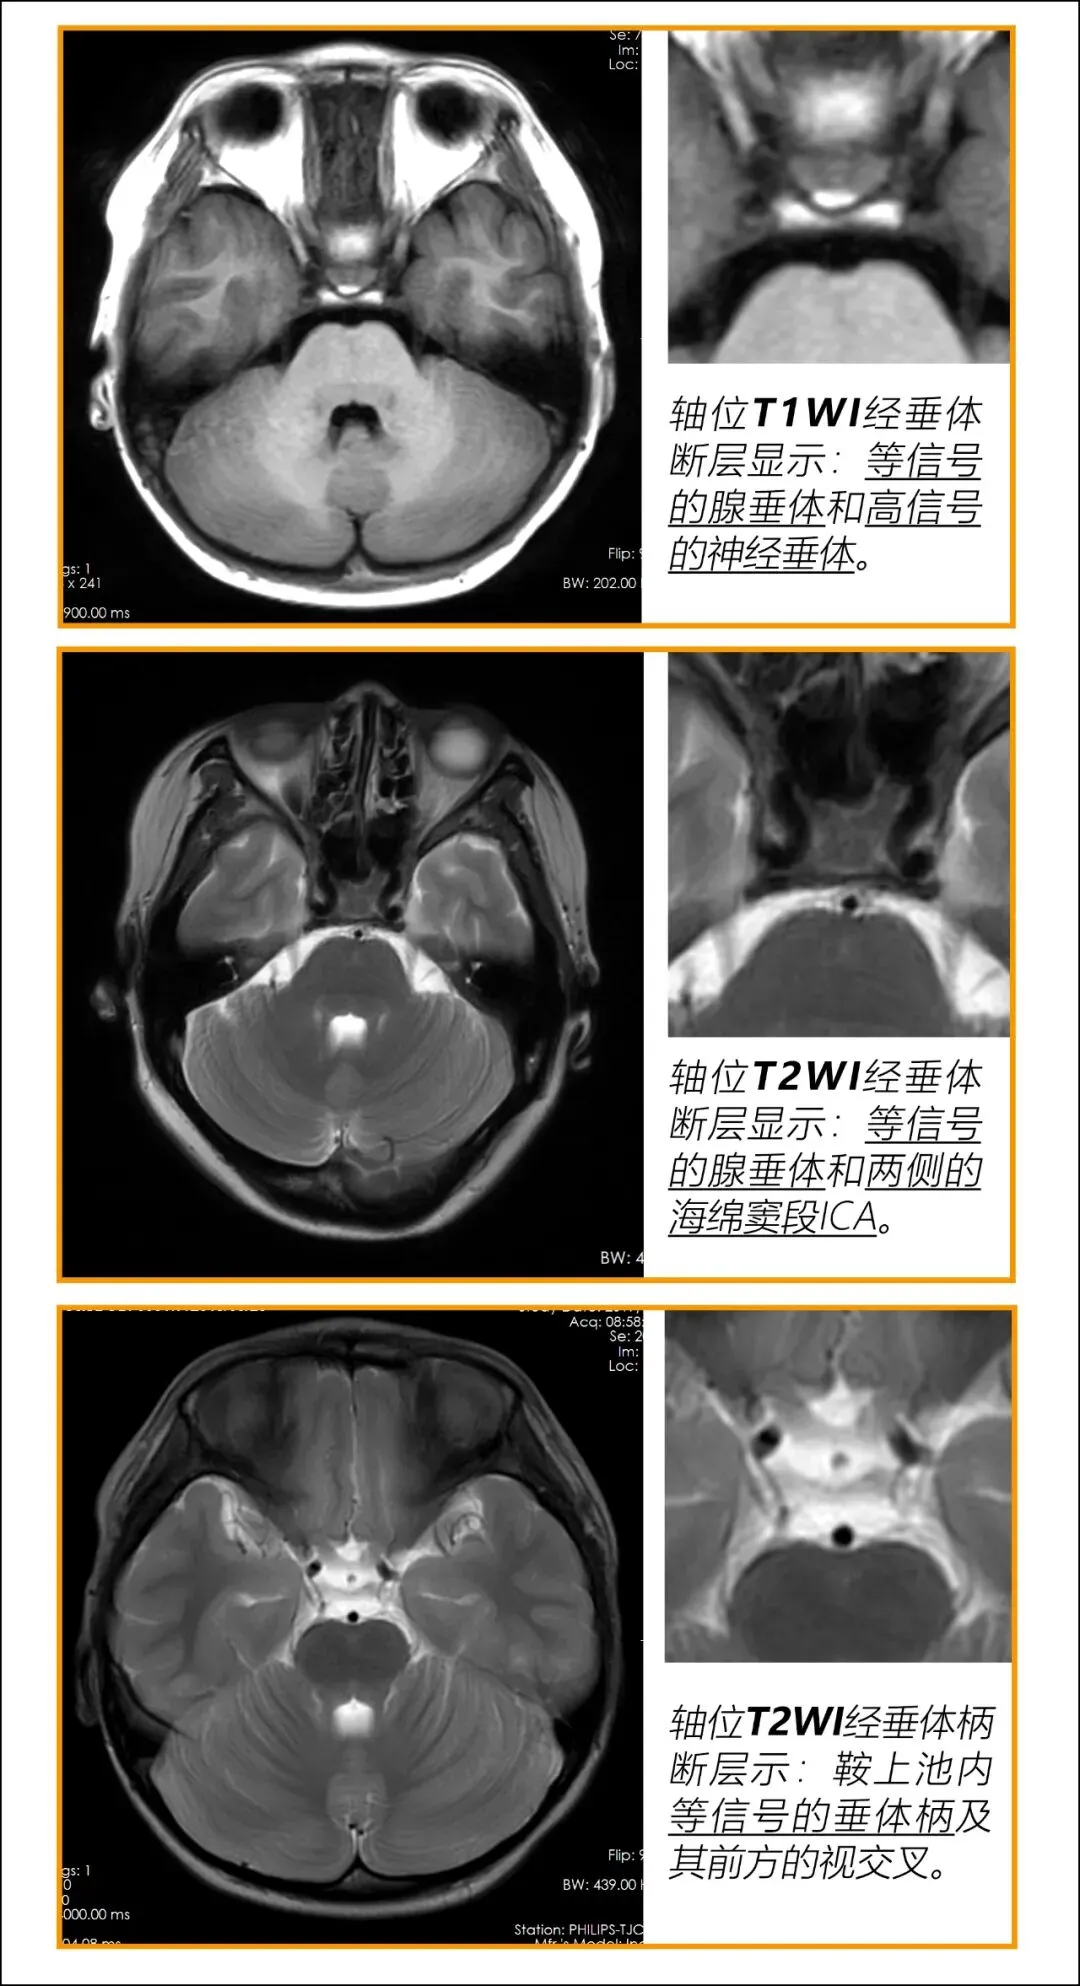

(一)在冠、矢、轴三种断面上认识垂体

3. 轴位

1. 腺垂体等信号:

T1WI上腺垂体与颞叶白质信号相似。

2. 神经垂体高信号:

目前公认,T1WI蝶鞍后部高信号代表了垂体后叶血管加压素的存储。